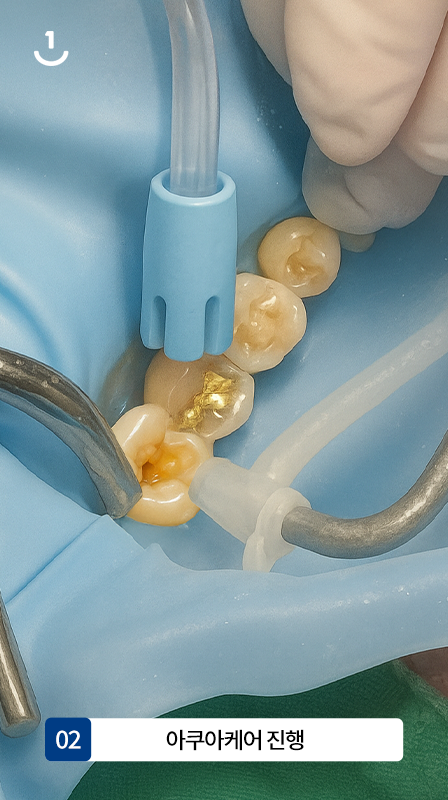

02

아쿠아케어 진행